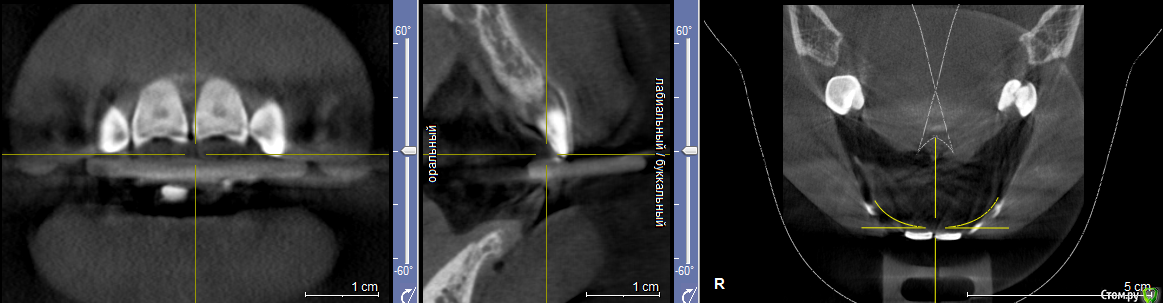

svetanik8 Опубликовано 25 мая, 2017 Поделиться Опубликовано 25 мая, 2017 Уважаемые врачи, прошу совета, чтобы определиться с тем, что делать.Году на 28м узнала, что у меня неправильный прикус (прямой), с детства отсутствует нижний передний зуб (детская травма, на тот момент врачи сказали, что зубы сойдутся, все будет ок, не сошлись, но мало кто видит, что его нет, улыбка как бы не такая низкая, чтобы открывать нижний ряд зубов).Лет в 25 удалили первую 6ку в нижнем ряду, спустя пару лет вторую симметрично, итого имею три проблемы, которые нужно решить (имплантация либо мост). Посетила пару врачей, один ортодонт предложил установить брекеты только на несколько нижних зубов с тем, чтобы сделать место для импланта на месте отсутствующего переднего, так как прикус меня 30 лет до этого не беспокоил, мне зубы кажутся ровными. Врач имплантолог в этой же клинике предложил по всем трем отсутствующим зубам сделать какое-то расщепление с подсадкой, при котором сразу же ставится имплант, причем обе шестерки предложил объединить в одну операцию, чтобы сэкономить на какой-то мембране.Второй врач сказал делать подсадку ткани по всем трем, по брекетам ничего не прокомментировал, отдельно нужно общаться с ортодонтом.И еще один врач тоже сказал, что нужно делать подсадку костной ткани, что расщепление ему не очень нравится в принципе, что может отломаться кость и тп. Подсадка костной ткани очень недешевая процедура (или я ходила в такие клиники дорогие, не знаю). Вопрос, стоит ли в моем случае делать импланты (по каждому зубу) или где-то лучше мост (например, семерка слева под коронку уже, там ползуба нет).Прилагаю снимки ОПТГ и КТ (скриншоты, если нужны другие ракурсы скажите, пока не разобралась как их делать).Отдельный вопрос по брекетам, не знаю выносить ли в отдельнуютему, проблема комплексная. На всякий случай еще фото обычные зубов.Спасибо заранее. Ссылка на комментарий

колесников Опубликовано 26 мая, 2017 Поделиться Опубликовано 26 мая, 2017 тактика зависит от предпочтений и умений доктора. все вышеизложенные методы могут быть применимы в вашем случае. с костной пластикой или без-это детали.Я бы не проводил костных пластик ,но это мое видение.Вобласти 31 необходима предварительная ортодонитеская подготовка Ссылка на комментарий

svetanik8 Опубликовано 29 мая, 2017 Автор Поделиться Опубликовано 29 мая, 2017 Я бы не проводил костных пластик ,но это мое видение. под костной пластикой подразумевается отдельная операция или расщепление тоже считается костной пластикой? По нормам мало мм объясняли, хотя по шестеркам одна врач совсем молодая говорила может сделать без подсадки. Ссылка на комментарий